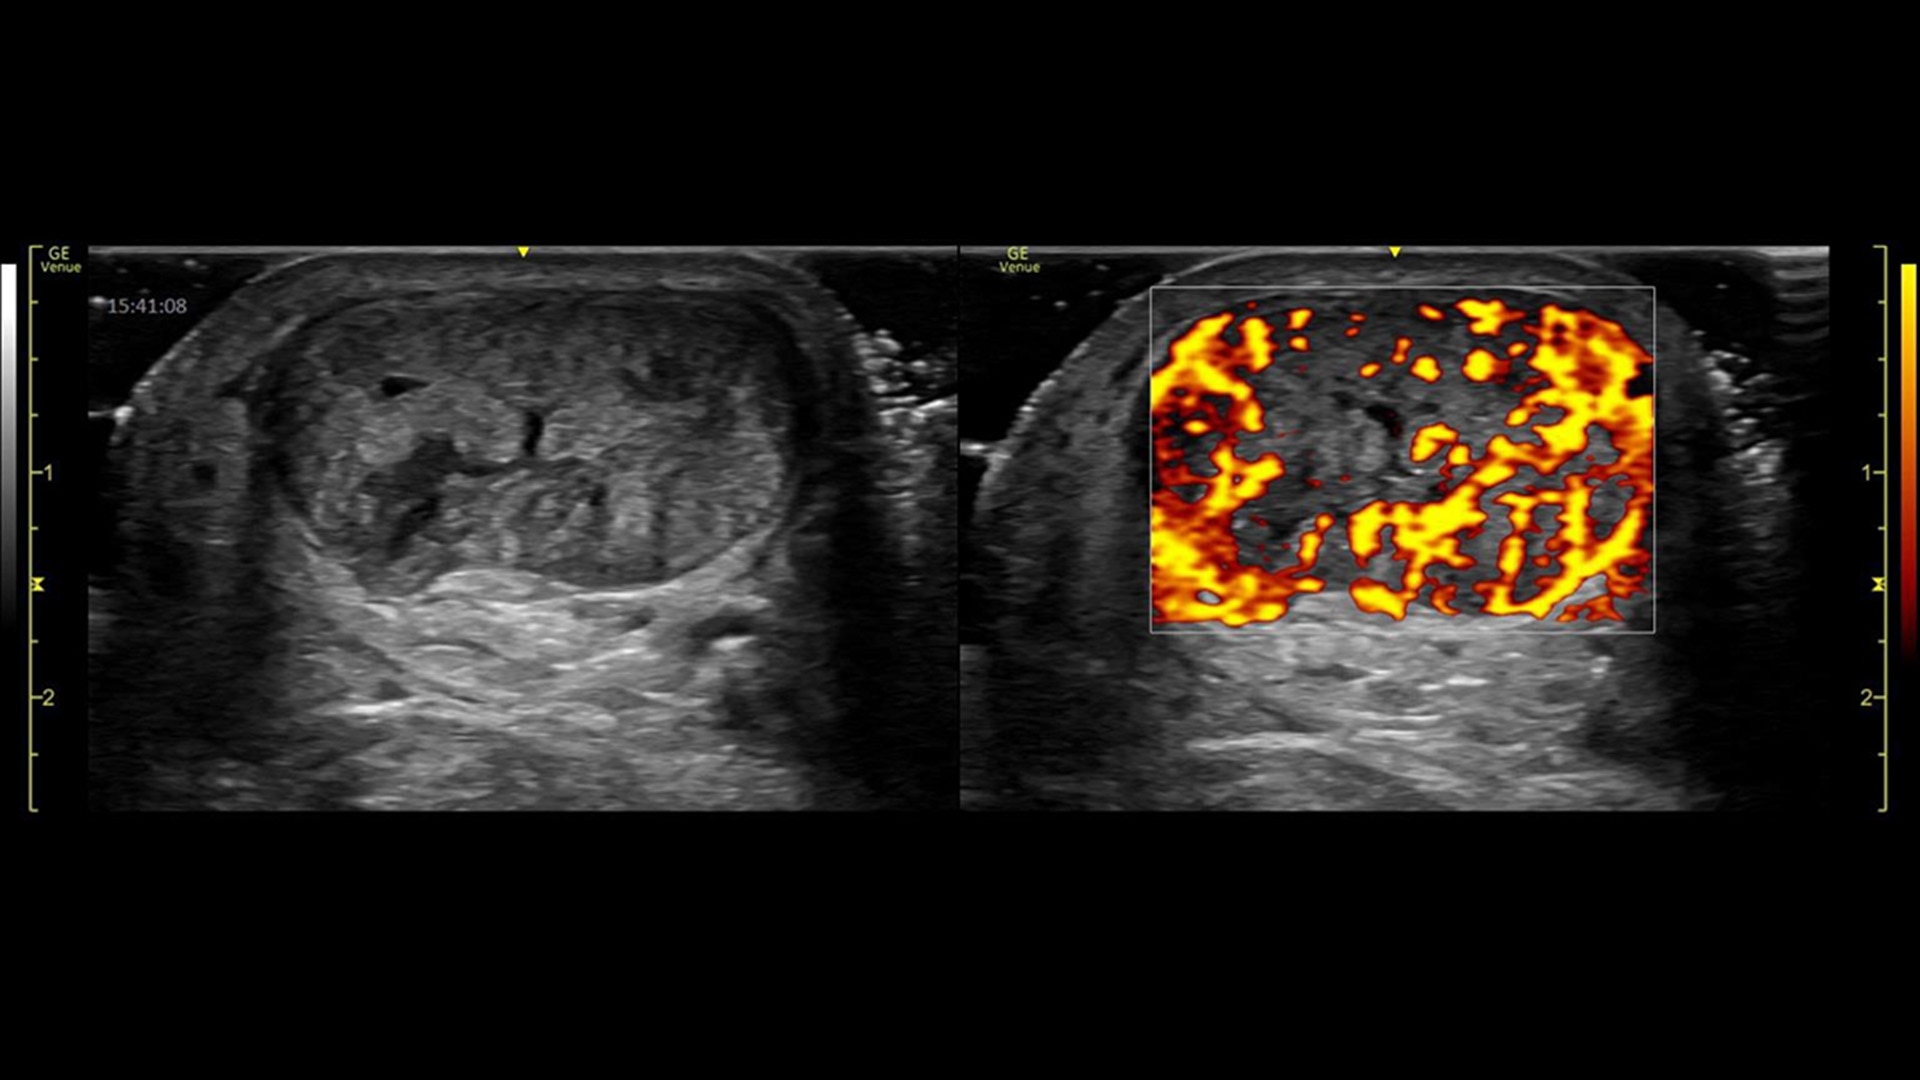

Power doppler imaging

Visualize slower blood flows

Power Doppler Imaging + (PDI+) is a color flow mapping technique used to map the strength of a Doppler signal coming from the flow rather than the frequency shift of the signal. In PDI+ mode, the sensitivity of the color in the Region of Interest (ROI) increases. Providing a higher resolution than the regular PDI mode, PDI+ is best used for slower blood flows such as those found in wrists, ankles, hands, and feet. This is an additional option that exists within the regular PDI mode.